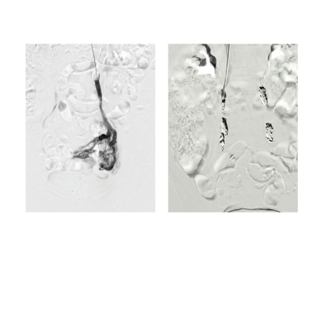

A 56-year-old male with a past medical history of gastroesophageal reflux disease and tobacco abuse presented to the emergency department with a chief complaint of chest pain and progressive shortness of breath of a year duration. The patient...